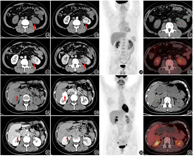

患者男,63岁,体格检查发现左肾占位5 d,无肉眼血尿、腹痛等不适。患者入院后完善腹部增强CT,可见左肾下极稍低密度肿块,大小为4.3 cm×3.5 cm×4.2 cm,增强扫描皮质期显著不均匀强化,实质期、排泄期强化逐渐减低(图1A,图1B,图1C,图1D)。为明确左肾肿物性质及全身情况行18F-FDG PET/CT显像,可见左肾下极稍低密度肿物,显像剂摄取相当于周围肾实质,SUVmax 3.8(图1E,图1F,图1G)。